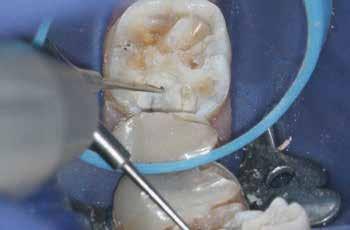

6. a–d. ábrák: A bal alsó második nagyőrlőfogon (3.7) kialakított konzervatív hozzáférési nyíláson keresztül végzett endodonciai kezelés lépései. A mezialis gyökér jelentős mértékben görbült. A gyökértömés hidraulikus kondenzációs technikával készült.

egyszerű obturációs technika, az anyag viszkozitási tulajdonságai és a pulpakamra viszonylag egyszerű tisztíthatósága a kezelésünk prognózisának veszélyeztetése nélkül teszi lehetővé az endodonciai beavatkozások lehető legkonzervatívabb módon történő kivitelezését. A bemutatott esetek ellátása során az Aurum Blue rendszert (Meta Biomed) használtuk a gyökércsatornák megmunkálására, míg a gyökértömés elkészítése során hideg hidraulikus kondenzációs technikát alkalmaztunk a kalcium-szilikát alapú CeraSeal (Meta Biomed) sealer felhasználásával (8. ábra).

Esetbemutatás (2., 3.)

Mindkét esetben irreverzibilis pulpitis miatt vált szükségessé a fogak endodonciai kezelése (6. a-d. és 7. a-b. ábrák). Az esetek ellátása során mindvégig minimálinvazív megközelítést alkalmaztunk. A hozzáférési nyílás kialakításától kezdve az endodonciai kezelés befejezését követő csonkfelépítésig, minden beavatkozás ennek megfelelően történt.

A konzervatív módon kialakított hozzáférési nyíláson keresztüli végzett kezelések során az egyik legnagyobb kihívást a gyökértömés elkészítése jelenti. Az egyenes irányú hozzáférés hiánya, a korlátozott rálátás és a pulpakamra kisméretű hozzáférési nyílása miatt csökkent hatékonyságú tisztíthatósága mind olyan faktorok, amelyeket figyelembe kell venni, ha minimálinvazív hozzáférést alakítunk ki.15 A kalcium-szilikát alapú sealerek fizikai tulajdonságai lehetővé teszik a klinikusok számára, hogy leküzdjék ezeket az akadályokat. A viszonylag